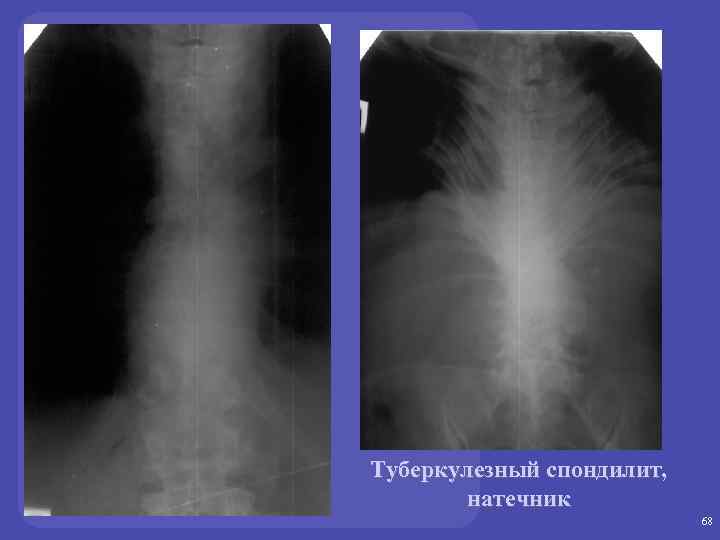

ТУБЕРКУЛЕЗНЫЙ СПОНДИЛИТ: Поражаются 2 -3 позвонка Преимущественное поражение – нижне-грудной и верхне-поясничный отделы Локализация туберкулезного остита – передне-верхние и передне-нижние отделы тел позвонков 65

ТУБЕРКУЛЕЗНЫЙ СПОНДИЛИТ: РЕНТГЕНОЛОГИЧЕСКИЕ СИМПТОМЫ - Снижение высоты межпозвонковых дисков - Разрушение тел позвонков и клиновидная деформация - Натечник - Блок позвонков 66

Туберкулезный спондилит 67

Туберкулезный спондилит, натечник 68